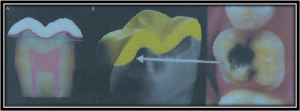

The Biodome crown preparation involves the meticulous preservation of as much healthy natural tooth structure as possible to mimic the natural form and function of a sound, healthy tooth.

This preparation technique is crucial to ensuring the longevity of the crown and tooth and maintaining the health of the pulp of the tooth

A traditional, full-coverage ceramic crown, while strong under compressive biting loads, is also quite weak under tensile loads as occurs with the wrap around the sides deeply to below the gum level.

The result is a tooth less likely to have any nerve problems, a much stronger tooth, and a margin between the crown and the tooth which is in an area easily maintained and cleaned compared to below the gum margin in a traditional crown.